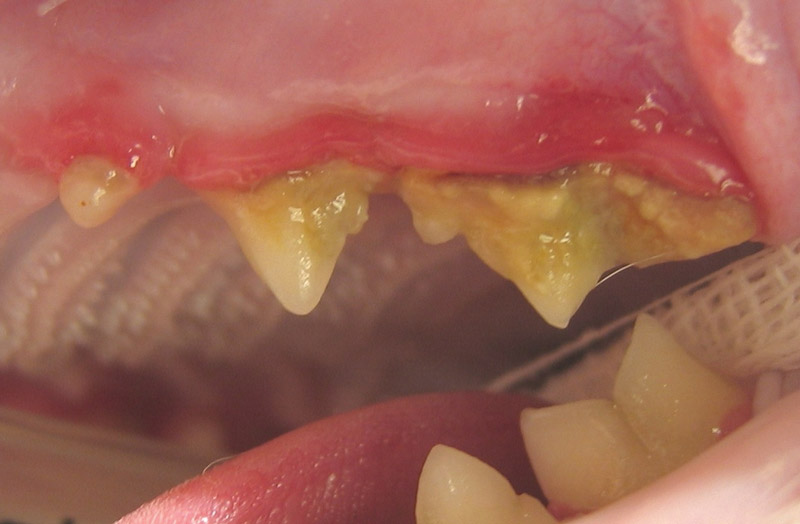

Research shows that ‘periodontal disease’ – a collective term for several inflammatory conditions in the mouth – occurs in 70% of cats by the time they are three years old*. You may not even be aware that anything is wrong because the symptoms can be hard to detect but, as well as causing painful damage inside a cat’s mouth, if left untreated, the bacteria involved can go on to affect other parts of their body. This means looking after your cat’s mouth should be an important part of your preventative health regime. Fortunately, there are some simple steps you can take to help maintain your cat’s oral health and in so doing, save them from potentially great discomfort and pain. To find out more, ask your vet or vet nurse (or this could be visit a website if it’s for a practice).